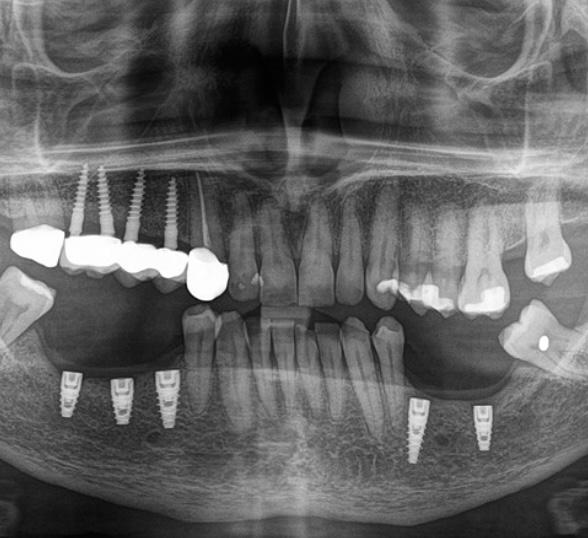

Un implante dental es una pieza de titanio o zirconio que se inserta quirúrgicamente en el hueso maxilar o mandibular para reemplazar la raíz del diente perdido.

Sobre ese implante se coloca una corona o prótesis, que recupera la función masticatoria y la estética de forma natural.

implantes dentales cali

odontología Cali